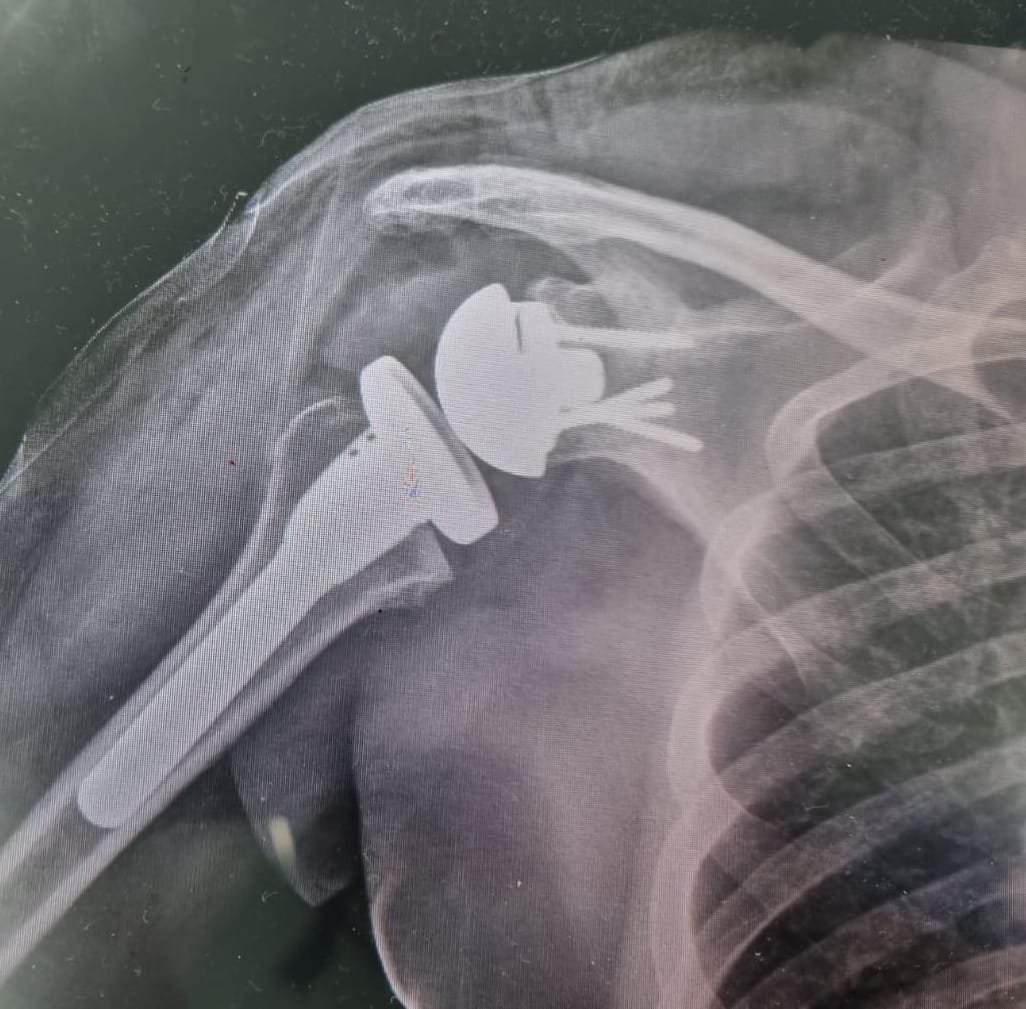

El Dr. José Luis Rodríguez García cuenta con el título de Especialista en Ortopedia y Traumatología.

Su compromiso con la salud y el rendimiento deportivo lo ha llevado a colaborar con la FIFA, aportando su experiencia médica en el cuidado, recuperación y prevención de lesiones de alto nivel competitivo.